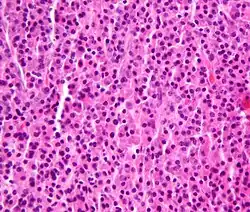

_HE_stain.jpg) Bone marrow aspirate showing the histologic correlate of multiple myeloma under the microscope, H&E stain

Bone marrow aspirate showing the histologic correlate of multiple myeloma under the microscope, H&E stain -

Histopathology

A bone marrow biopsy is usually performed to estimate the percentage of bone marrow occupied by plasma cells. This percentage is used in the diagnostic criteria for myeloma. Immunohistochemistry (staining particular cell types using antibodies against surface proteins) can detect plasma cells that express immunoglobulin in the cytoplasm and occasionally on the cell surface; myeloma cells are often CD56, CD38, CD138, and CD319 positive and CD19, CD20, and CD45 negative.[21] Flow cytometry is often used to establish the clonal nature of the plasma cells, which will generally express only kappa or lambda light chain. Cytogenetics may also be performed in myeloma for prognostic purposes, including a myeloma-specific fluorescent in situ hybridization and virtual karyotype.

The plasma cells seen in multiple myeloma have several possible morphologies. First, they could appear like a normal plasma cell, a large cell two or three times the size of a peripheral lymphocyte. Because they are actively producing antibodies, the Golgi apparatus typically produces a light-colored area adjacent to the nucleus, called a perinuclear halo. The single nucleus (with a single nucleolus with vesicular nuclear chromatin) is eccentric, displaced by an abundant cytoplasm. Other common morphologies seen, but which are not usual in normal plasma cells, include:

- Bizarre cells, which are multinucleated

- Mott cells, containing multiple clustered cytoplasmic droplets or other inclusions (sometimes confused with Auer rods, commonly seen in myeloid blasts)

- Flame cells, having a fiery red cytoplasm[71][72]